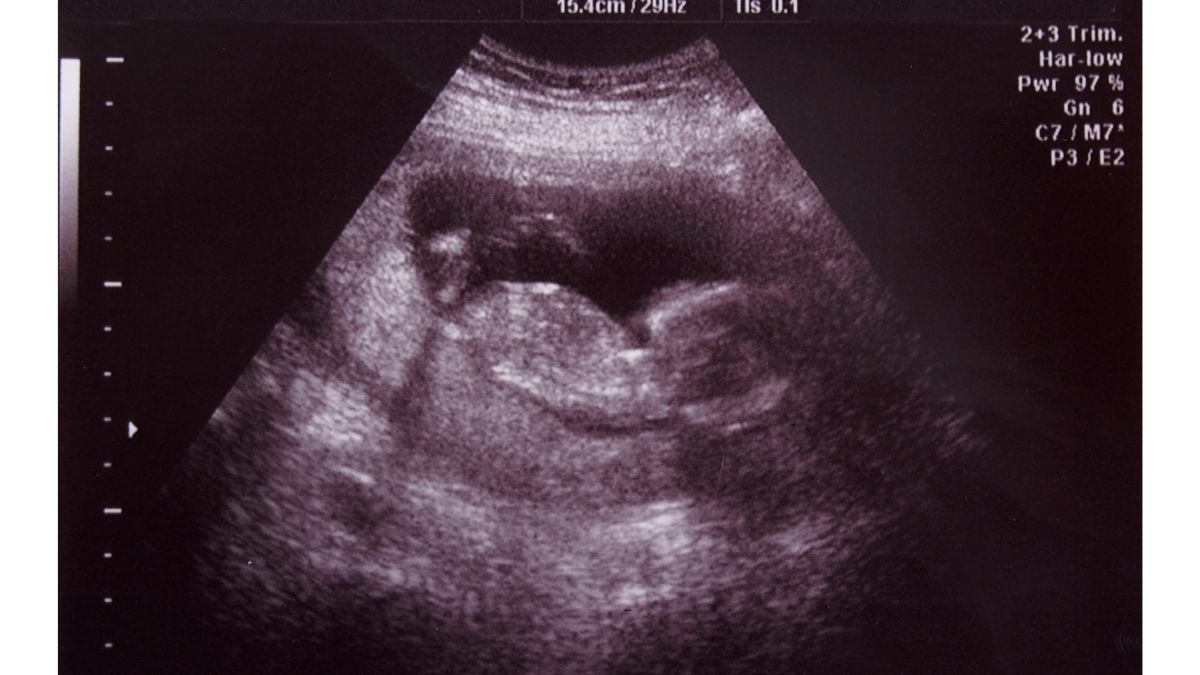

Untuk lebih memastikan kehamilan, Anda dianjurkan untuk melakukan pemeriksaan ultrasonografi (USG) di dokter atau bidan. Saat pemeriksaan tersebut dilakukan, tim dokter atau bidan biasanya akan melihat ada/tidaknya gestasional sac pada ibu hamil.

Gestasional sac biasanya akan terdeteksi melalui pemeriksaan USG, dan bisa ditemukan di dalam rahim. Pada pemeriksaan tersebut, gestasional sac akan tampak seperti kantung putih dengan area pusat yang jernih.

Menurut dr. Atika, kantung kehamilan akan terdeteksi ketika kehamilan menginjak usia 4–5 minggu sejak hari haid terakhir pada pemeriksaan USG transabdominal (dari perut).

Namun, pada pemeriksaan USG transvaginal (dari vagina), gestasional sac dapat terdeteksi pada kehamilan usia 3–5 minggu.

Mengapa bisa berbeda? USG transvaginal memiliki sensitivitas tinggi dan menghasilkan gambar lebih jelas dibandingkan USG transabdominal. Kantung kehamilan biasanya dapat terlihat setelah kadar hCG berada di kisaran 1500 dan 2000.